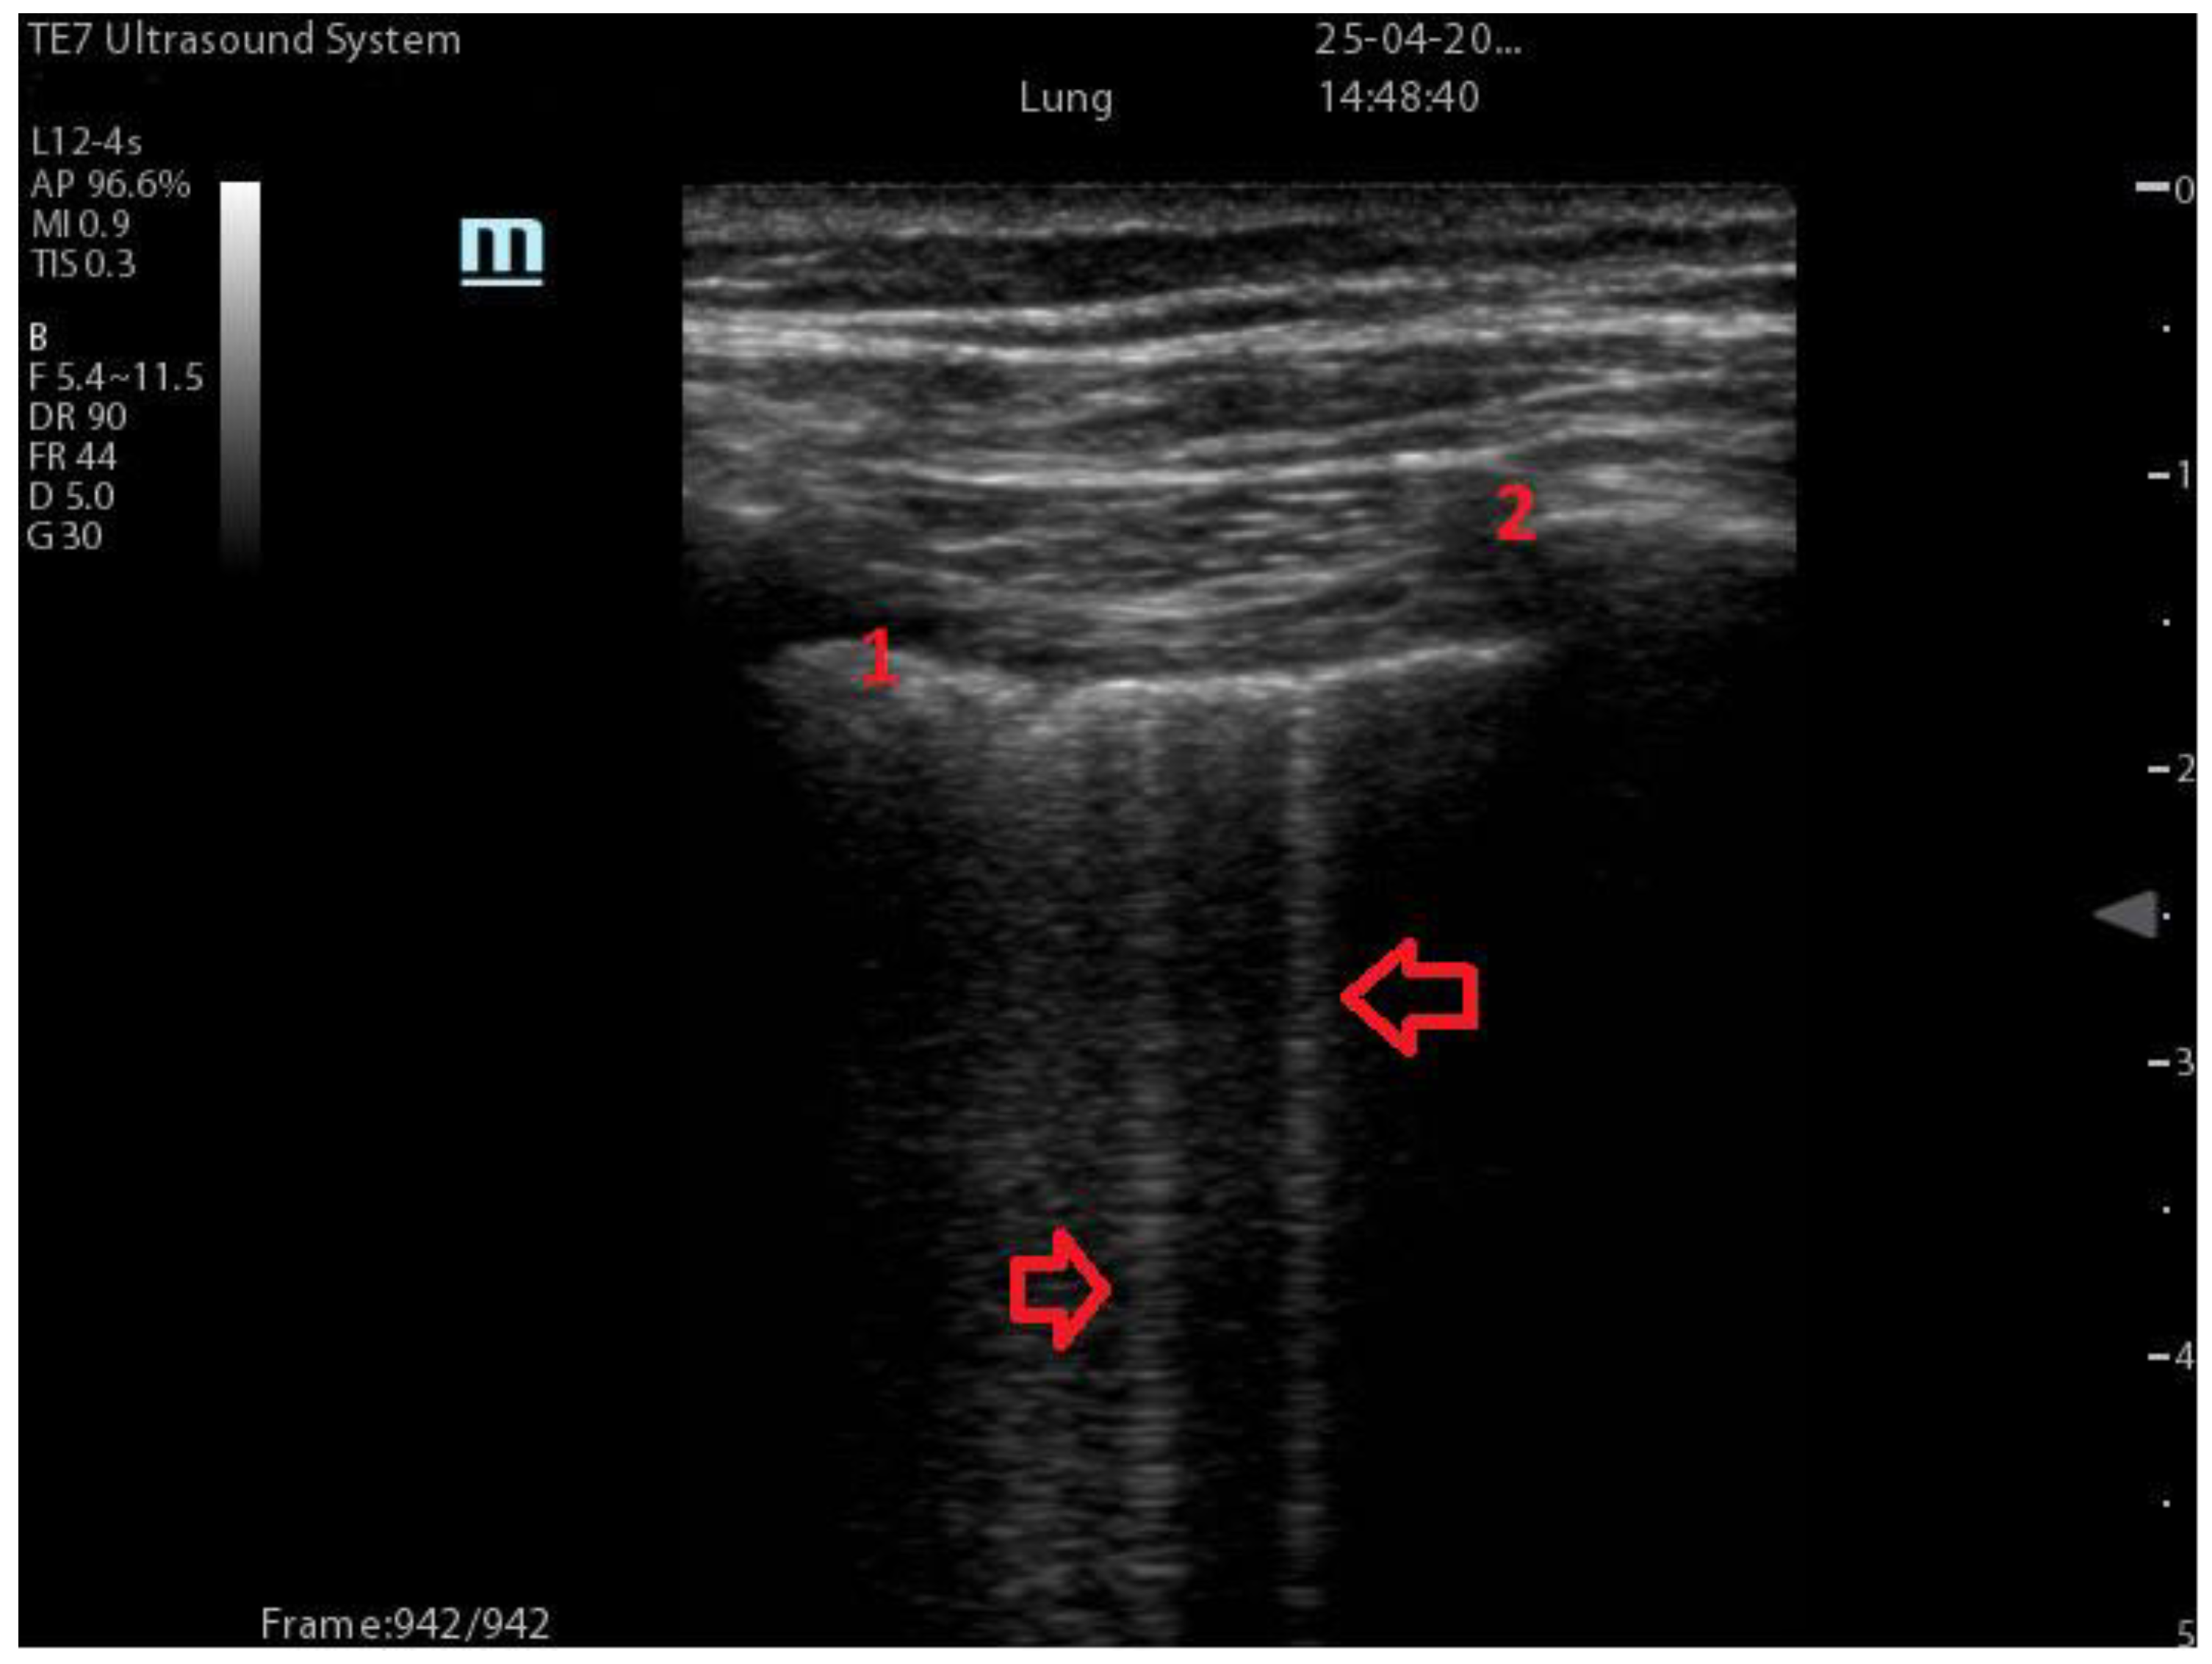

| Coalescent Lung score c-LUS [10,11] | Score 0: presence of A-lines, maximum 2 B-lines Score 1: ≥3 well-spaced B-lines Score 2: coalescent B-lines Score 3: tissue-like pattern | ![]() 12 AREAS |

| Quantitative LUSS (q-LUS) [12] | Score 0: A-lines, maximum 2 B-lines Score 1: artefacts occupying ≤ 50% of pleura Score 2: artefacts occupying > 50% of pleura Score 3: tissue-like pattern | ![]() 12 AREAS |

| Soldati Score [36] | Score 0: continuous and regular pleural line, presence of A-lines. Score 1: indented pleural line, with the presence of vertical white areas. Score 2: broken pleural line with the appearance of small-to-large consolidations associated with white lung. Score 3: dense and largely extended white lung with or without consolidations. | ![]() 14 AREAS |